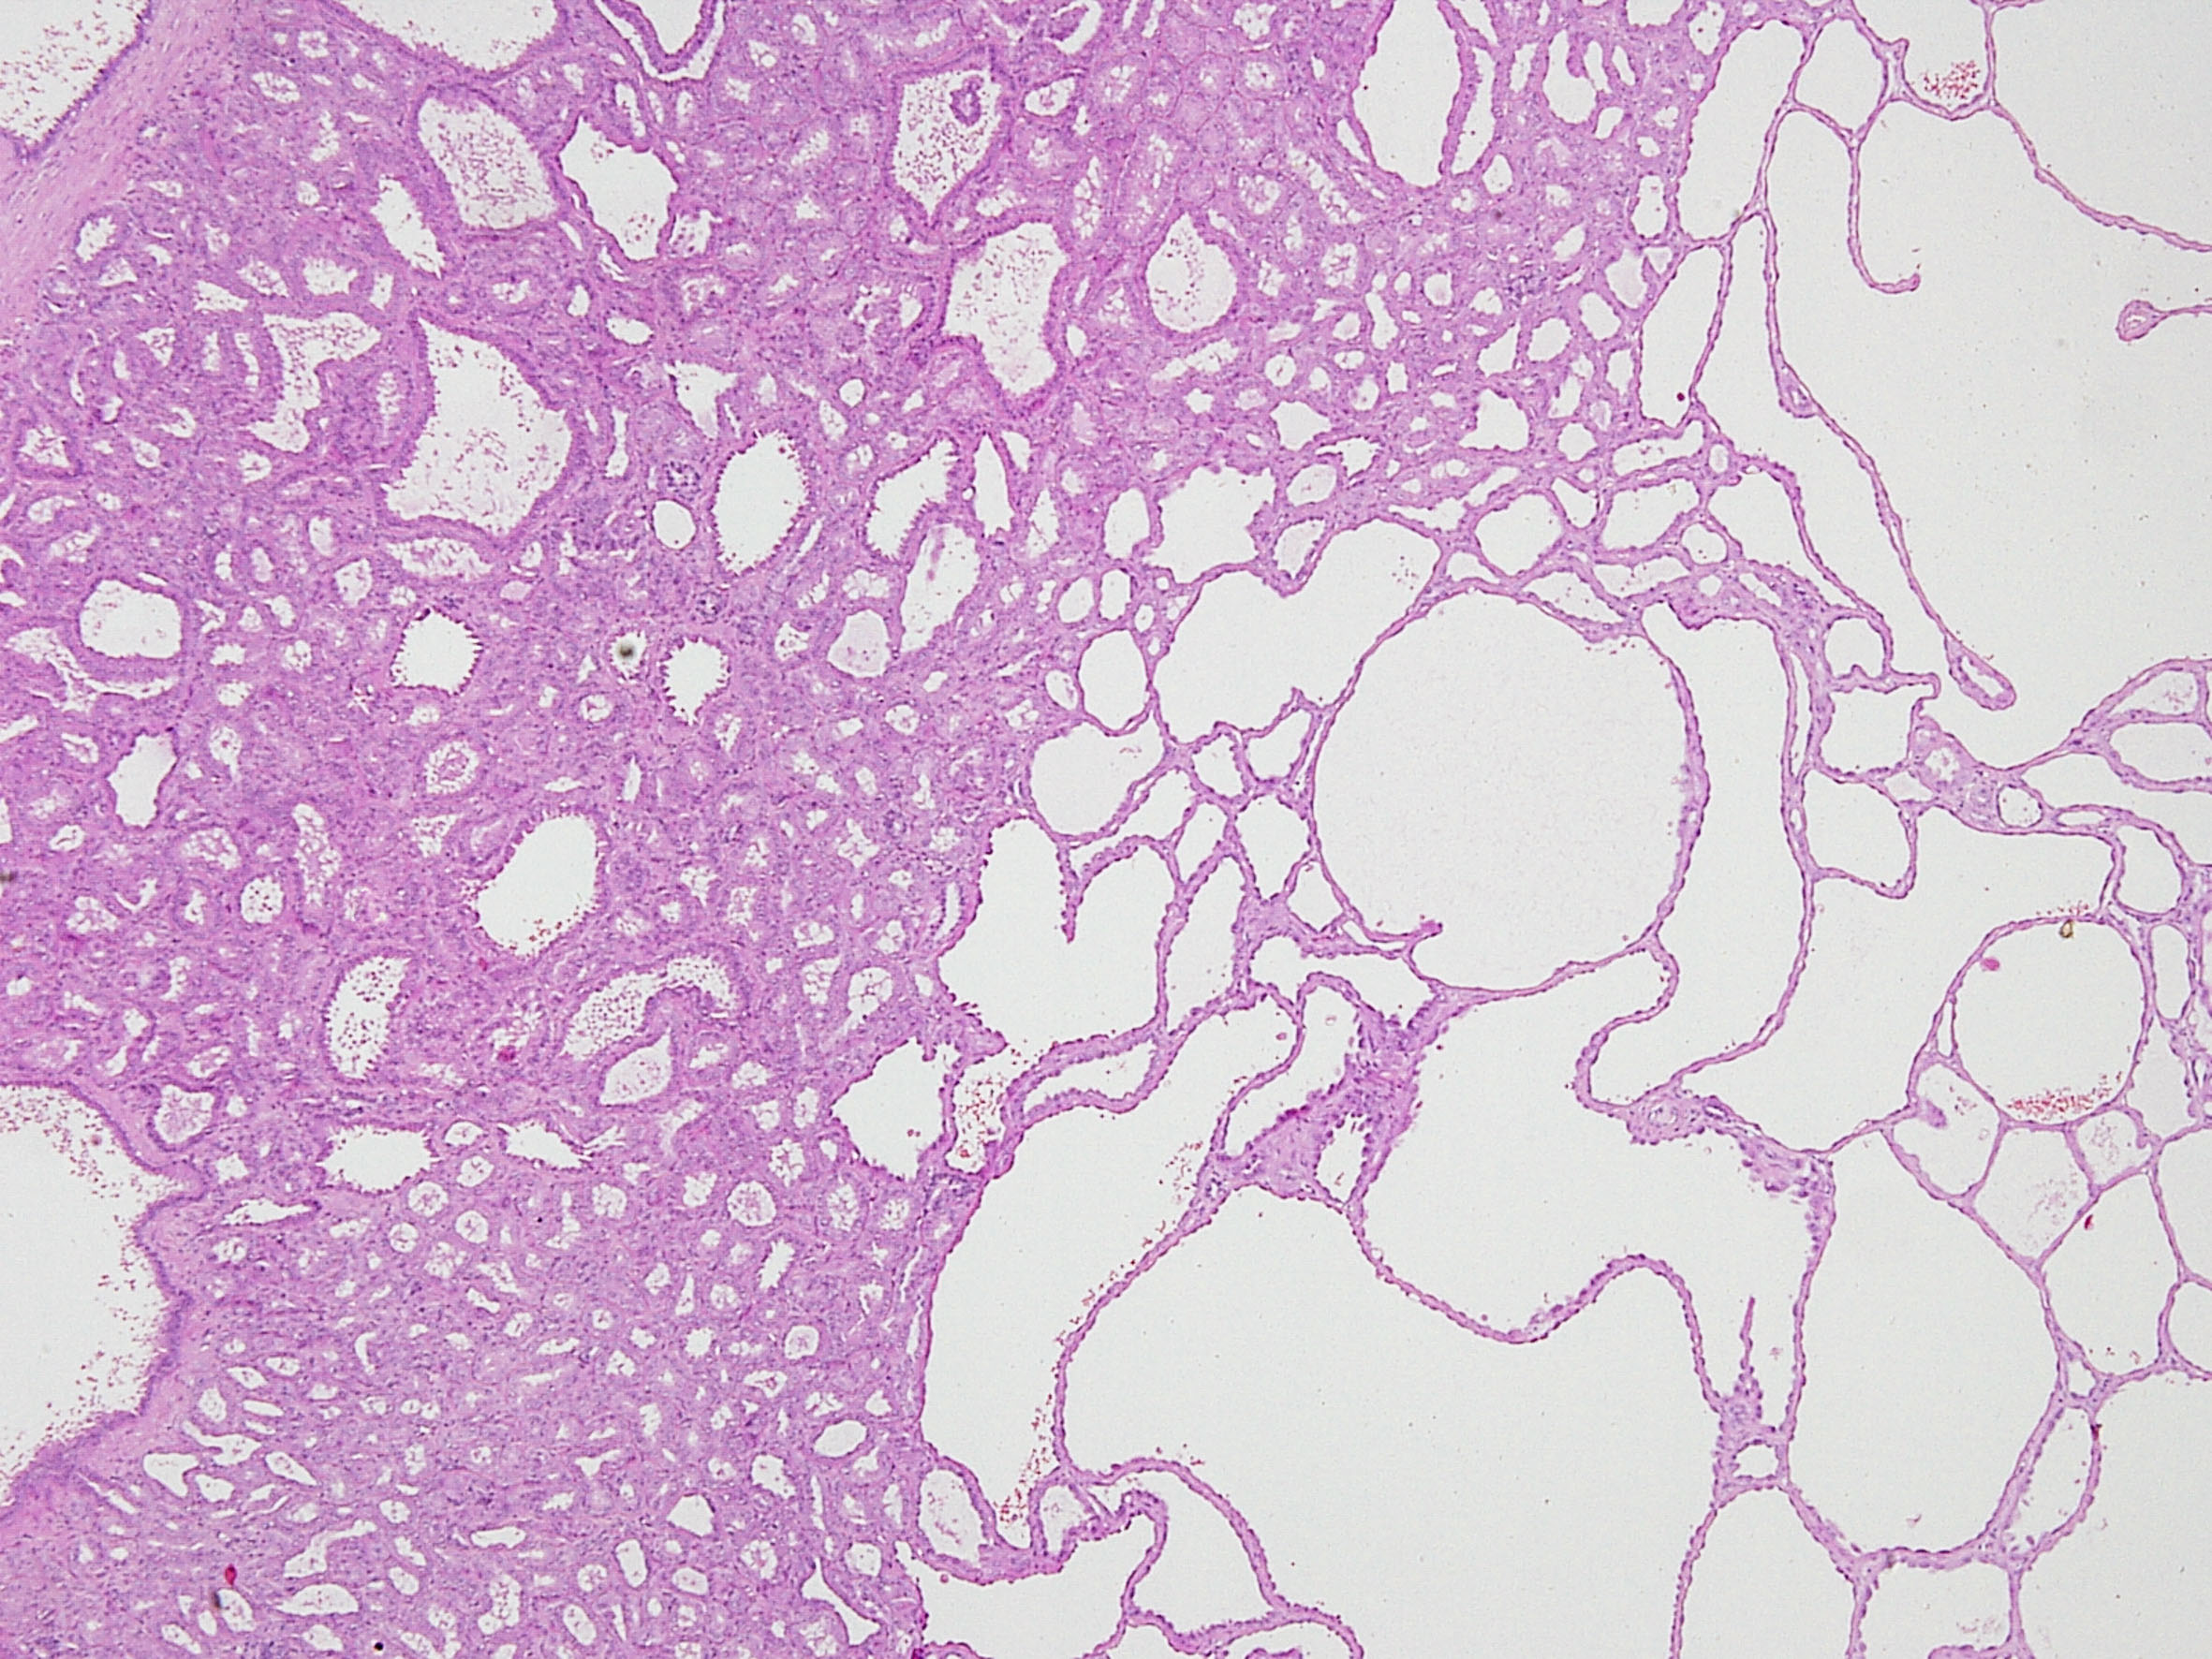

Consensus grade: Tubulocystic RCC

Tubulocystic renal cell carcinoma